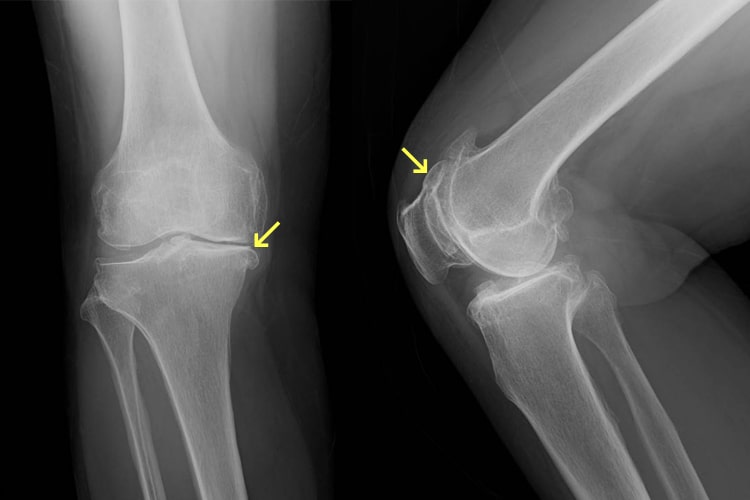

半月板損傷

半月板損傷は膝関節の屈伸と回旋との協調運動が破綻した時に発生します。原因はスポーツ外傷によるものが多く、その他では転倒、捻挫、交通事故等があります。損傷によって、膝の曲げ伸ばしの際に痛みやひっかかりを感じたりします。ひどい場合には、膝に水(関節液)がたまったり、急に膝が動かなくなる“ロッキング”という状態になり、歩けなくなるほど痛くなります。治療としてはリハビリテーション療法、膝サポーター、ステロイド、ヒアルロン酸の関節内注射等、保存的治療での症状改善を目指します。保存的治療で改善しない場合には手術を行います。手術法には切除術(損傷した部分を切り取る)と縫合術(損傷した部分を縫い合わせる)の2種類があり、症状に合わせて選択します。